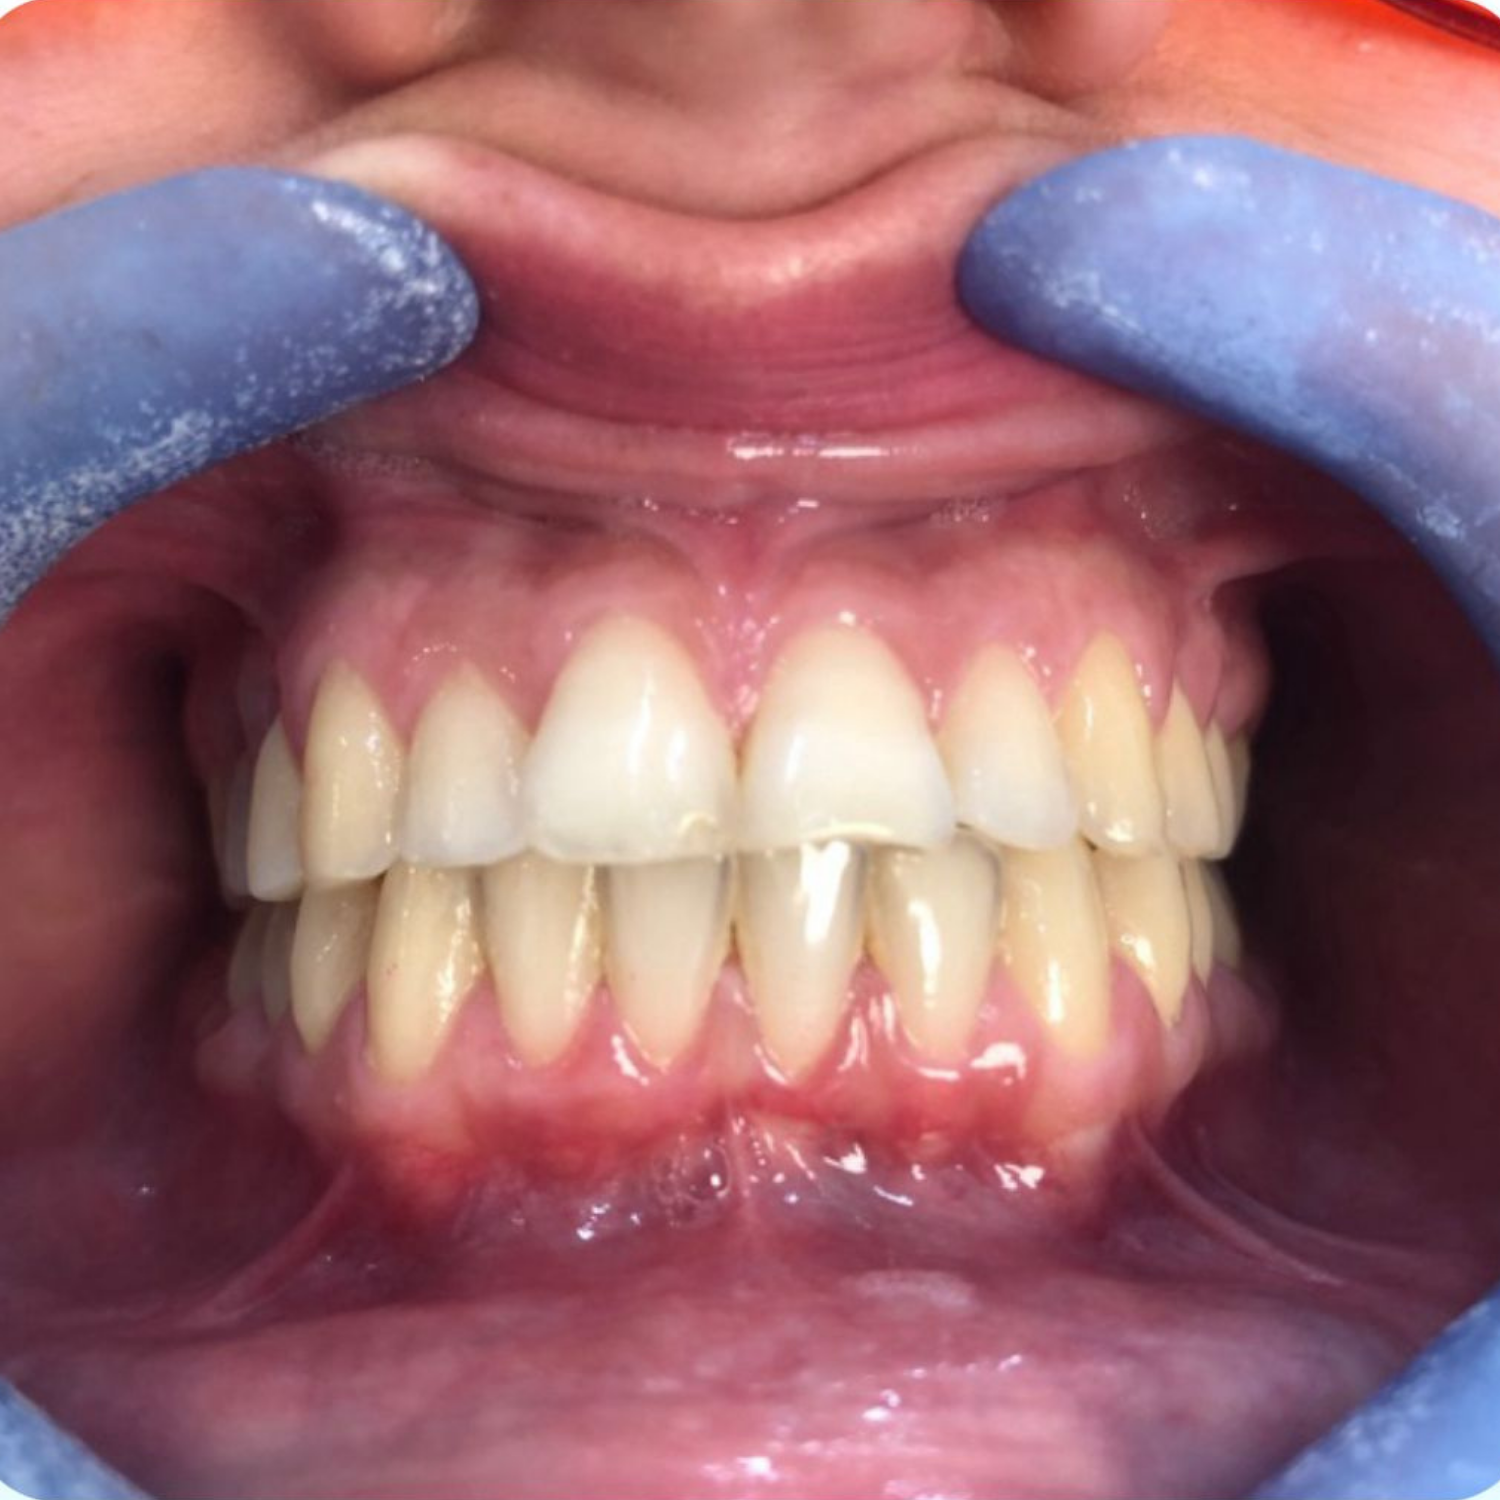

ll caso piu complesso di sbiancamento dentale: paziente con discromie gravi da assunzione di tetracicline. ​

Trattato con piu sedute di sbiancamento medicale alla poltrona e più cicli di trattamento domiciliare.